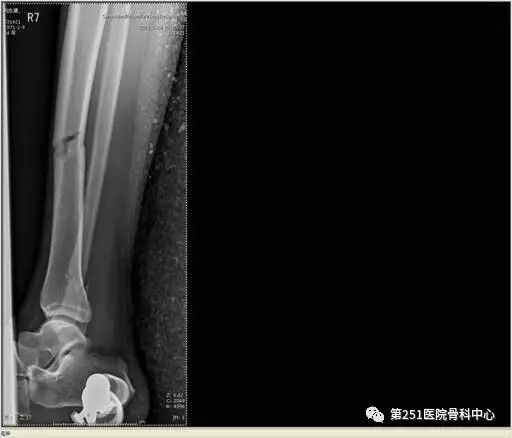

病例6:男性,39岁,车祸伤SchatzkerⅥ型胫骨平台骨折。

![]()